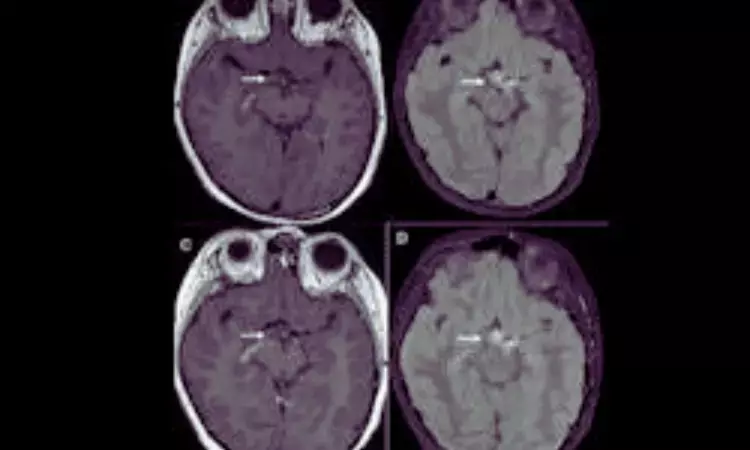

- Both betanin and BBCAs produced visible contrast enhancement in the gastrointestinal tract, parenchymal organs, and vascular structures, indicating effective imaging capability.

- Notably, liver enhancement following BBCA administration was particularly prominent.